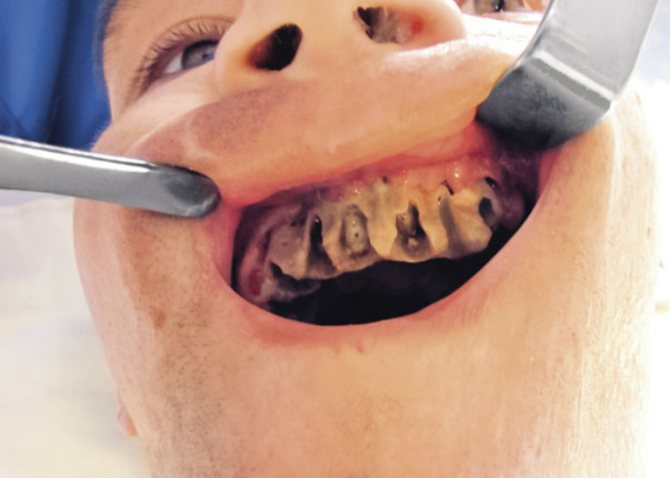

- Альвеолит. Заболевание начинается незаметно, но затем быстро развивается, охватывая ткани десны, кость. Признаки этого осложнения появляются на третьи сутки после удаления зуба, на вторые – после удаления зубы мудрости. Болевые ощущения нарастают от ноющих и периодических до стреляющих и постоянных. Боль распространяется на челюсть, определяется по расположению тройничного нерва, иррадиирует в висок и в шею. Если был удален один из моляров, например, зуб мудрости, то боль отдает в ухо. Становится сложнее открывать рот. Увеличивается отек десны и щеки, покраснение слизистой переходящее в цианоз. Лечение альвеолита основано на приеме антибиотиков, антисептиков и противовоспалительных препаратов.

- Воспаление надкосницы. Проявляется набуханием и болезненностью десны. Боль усиливается при механическом воздействии. Воспаление распространяется на ближайшие участки: появляется отечность щеки, губ, подбородка, шеи. Температура тела часто достигает 38°C, а в некоторых случаях может быть и выше. Боль иррадиирует на половину головы. Образуется белый налет на мягких тканях. Через некоторое время в десне появляется гной, выходящий через рану. Лечебные мероприятия включают в себя очищение раны от гноя, ее дезинфекцию, прием антибиотиков и анальгетиков.

- Абсцесс. Травмы тканей ротовой полости в ходе операции неизбежны. Они оказываются более серьезными при удалении зуба мудрости из-за его расположения и некоторых других особенностей. Вследствие этого может появиться гнойный абсцесс, потому что рана – идеальная среда для размножения патогенных микроорганизмов. Образуется гной, который может перейти в мягкие ткани. Причиной абсцесса после процедуры удаления зуба, наиболее часто является несоблюдение рекомендаций стоматолога. Лечение включает в себя очищение от гноя, прием противовоспалительных препаратов и антибиотиков. Медикаментозное лечение прописывается исключительно врачом, самостоятельный подбор антибиотиков может принести больше вреда, чем пользы.

Остеомиелит

Воспаление костной ткани, возникающее после удаления зуба. Такое осложнение бывает нечасто, проявляясь в случае нелеченого альвеолита. Характеризуется оно изменениями артериального давления, повышенной температурой тела, постоянными болями, увеличением лимфоузлов. Воспалительный процесс негативно влияет на весь организм, что отражается на результатах анализа мочи и крови.